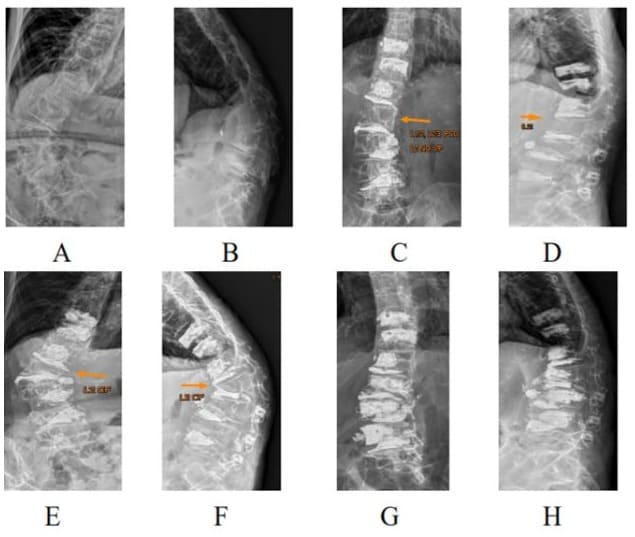

Degenerative Lumbar Scoliosis (DLS) may cause low back pain, leg pain, coronal imbalance and disability [1,2] and sometimes, surgery, including spinal decompression or fusion, is recommended. However, posterior instrumentation with bone grafts for the treatment of DLS is not only time consuming, but also has an elevated risk of complications [3,4]. The high incidence of operation complications leading to an advancement as an alternative treatment has launched in the past decade, i.e., Percutaneous Cement Discoplasty (PCD). This procedure was intended to decrease spinal instability for the advanced disc degeneration and promise clinical results with low complication rates have been reported [5-10]. PCD has been reported as an excellent target therapy for pain relief, but comparatively poor for spinal stenosis and scoliosis correction. PCD has no significant correction for lumbar lordosis or scoliosis and 14.7% of 156 PCD patients required second decompression surgery [5]. Due to osteoporosis in PCD elders, adjacent vertebral fractures may occur when scoliosis was corrected and increased stress in the vertebral bodies on the concave side (Figure 1).

Figure 1: A 68-year-old 32-kg female with degenerative scoliosis 70‘, thoracolumbar kyphosis 83’ (A, B) was treated with L3/5 open interbody cementation and L1/2, L2/3 cement discoplasties (C, D). An L2 compression fracture occurred one month later and caused re-kyphoscoliosis (E, F). L2 was reconstructed with one body cage with cementation and L3, L4 prophylactive vertebroplasties were done (G, H).